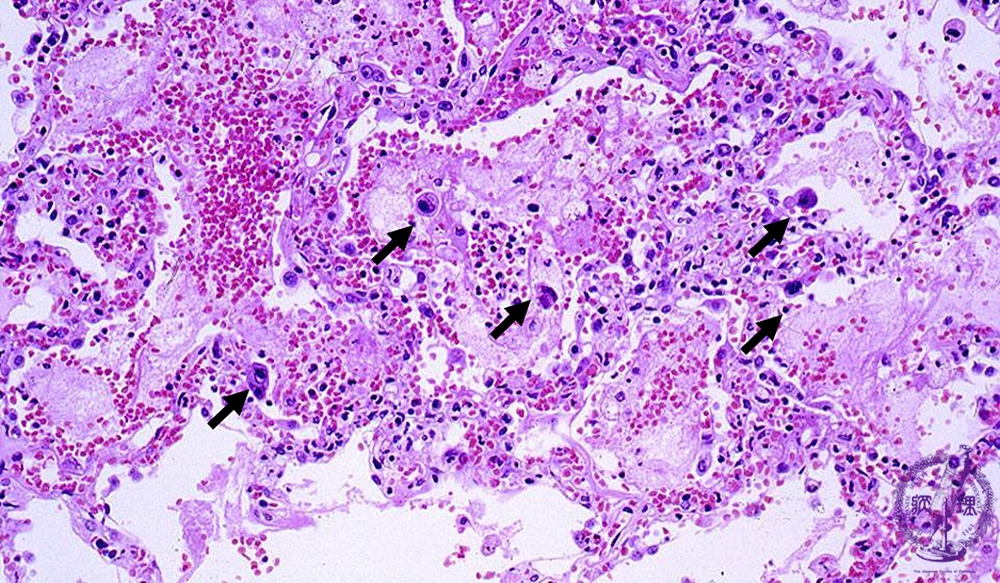

- ★(8)Viral pneumonia (cytomegalovirus inclusion body pneumonia)

Microscopic view (HE stain, low power view): The interstitial pneumonia pattern is shown. In this case, there are infiltrating neutrophils, necrosis, hemorrhage and scattered large cells with hyperchromatic nuclei (arrow).